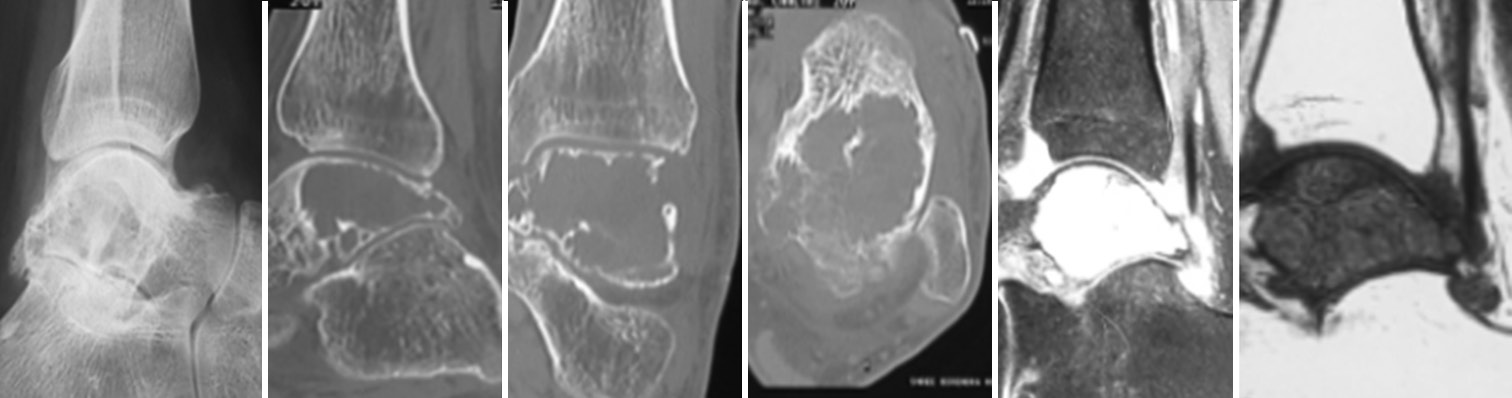

His X-ray of the left ankle joint [Figure 1(a)] revealed lytic lesion of the talus with some sclerotic changes with normal joint space. Hence, for further evaluation, we plan to go for computed tomography (CT) scan to define the lesion. His CT scan the left ankle [Figures 1(b-d)] revealed expanding lytic lesion of the talus involving dome, mid and posterior portion with cortical breach measuring 44*41 mm in size with intact ankle joint. Being CT scan was inconclusive, we plan to workup with magnetic resonance imaging left ankle [Figures 1 (e,f)] which showed multiloculated well-defined lesion of varying sizes in talus showing T1 hypointensity and T2 hyperintensity giving fluid-fluid level appearance suggestive of ABC.

Pre-operative lateral view of X-ray left ankle revealed lytic lesion with minimal sclerotic changes in talus. On further work-up with CT scan showed expanding lytic lesion of talus extending dome mid and posterior portion of talus with cortical breach (44*41mm) with intact ankle joint space. On pre-operative MRI there was multiloculated well defined lesion in talus showing T1 hypointensity and T2 hyperintensity suggesting ABC.